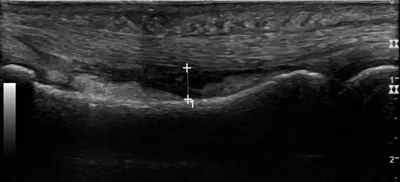

This collection contains 1 radiology images related to annular pulley, including various imaging modalities such as X-rays, MRIs, CT scans, and ultrasound images commonly used in medical diagnosis and education.